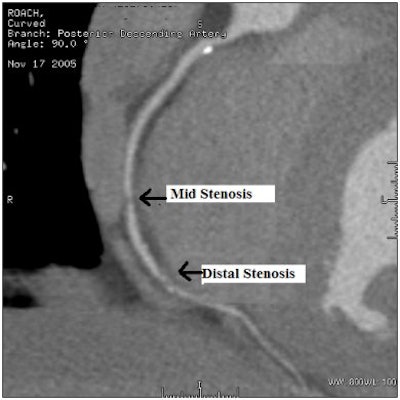

When the images came up we immediately saw one area of minor interest in my left coronary artery, and two areas of more significant interest in my right coronary artery, one mid and one distal. Occasionally, artifacts can be introduced into the images as a result of patient motion or through the reconstruction software. There are techniques to clear the artifacts, and so we began to attempt to clear them out of the images.

After about 10 minutes of work, the two areas remained. I just couldn't believe that I had what looked like two significant blockages of at least 70%. I asked Dr. Woolley to let me process the study. After additional work, Dr. Woolley said, "If this was any other 38-year-old patient, you'd be done with the exam and be recommending catheterization without hesitation." I realized he was right.

![]() |

| 64-slice CT angiography image demonstrates 70% stenosis in Dr. Roach's mid and distal right coronary artery. Image courtesy of Dr. Benjamin Roach. |